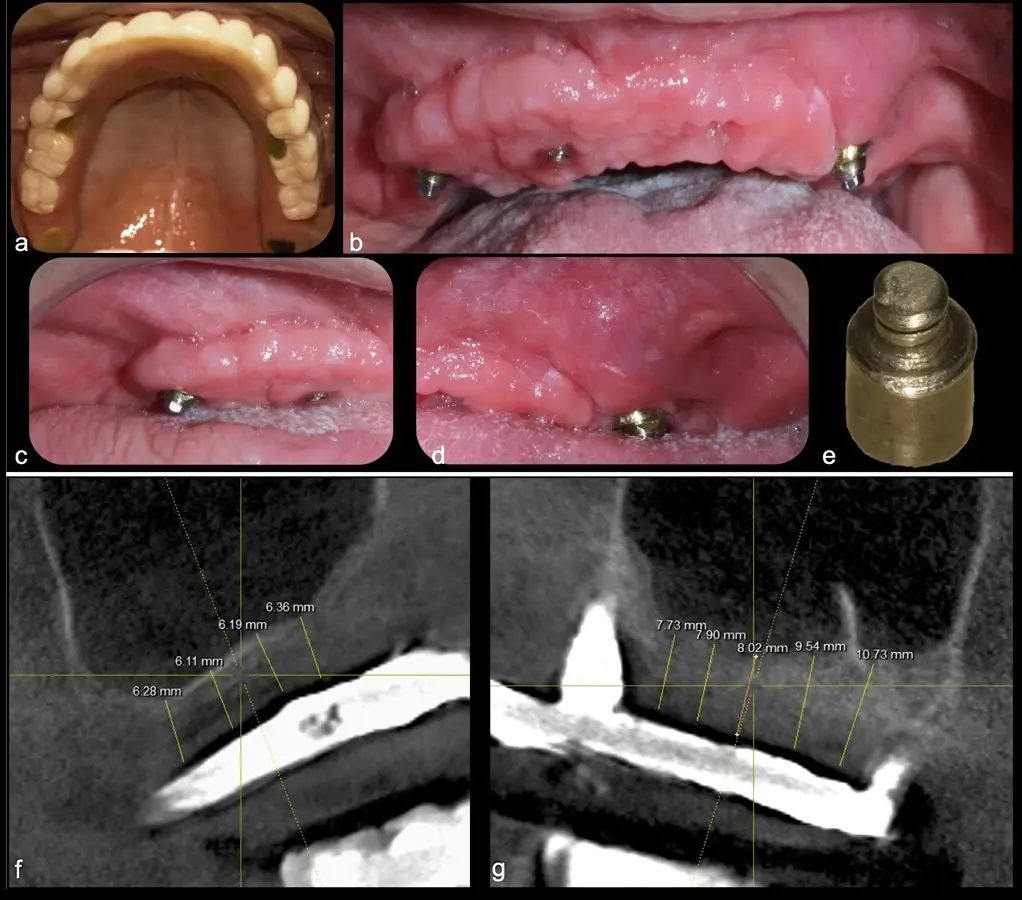

Paciente de 62 años, de sexo masculino, llega a la consulta para la colocación de implantes dentales. Refiere haber tenido tratamiento previo con implantes dentales, algunos de los cuales fueron perdidos. A la evaluación clínica se observa ausencia de piezas dentarias en el maxilar superior y 3 implantes remanentes. En la evaluación tomográfica se observa neumatización de los senos maxilares del lado derecho e izquierdo (Figura 14), para lo cual se indica el procedimiento quirúrgico de levantamiento de piso de seno maxilar en ambos cuadrantes, como paso previo a una nueva planificación implantosoportada.

Figura 14. Evaluación intraoral en donde se evidencia presencia de una prótesis híbrida soportada sobre implantes dentales, al retiro de la estructura se observó tornillo protésico fracturado (a, b, c). Evaluación tomográfica: corte sagital a nivel de los senos maxilares derecho e izquierdo, donde se observa una atrofia severa de los rebordes óseos acompañados de neumatización de los senos maxilar (d, f, g).

Figura 31. Control tomográfico post operatorio: corte sagital de ambos senos maxilares. (derecha e izquierda).